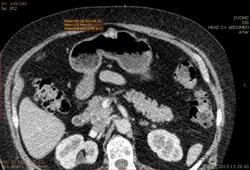

Пациентка 66 лет. В 2010 году мастэктомия слева - Cr II B ст., псориаз. Я нашел: образование нижнего полюса правой почки, образование в антральном отделе желудка по малой кривизне, киста яичника слева...в желчном пузыре много газосодержащих камней(?), лимфоузлов вроде не видно. Всё, кроме образования желудка находили ранее на УЗИ да на МРТ. Коллеги, посмотрите, можт я чё пропустил или неправильно понял. Какие мысли по поводу образований - особенно желудка(GIST? mts?)  DICOM здесь http://files.mail.ru/2C4F7CA79A884D37B3C86FF69C3D8D67

Мне кажется, что маловато контраста на вес пациентки. Почечно-клеточная (как более вероятная) карцинома правой почки, в стенке желудка написала бы мтс. Газосодержащие камни желчного пузыря. Кистовидное образование яичника. Киста печени, кисты почек. Дивертикулез толстой кишки. А что с жиром в грыже (вроде пупочная))) - наверное, последствие инфаркта сальника.